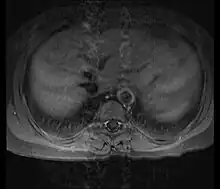

Although the cause of Takayasu arteritis is unknown, the condition is characterized by segmental and patchy granulomatous inflammation of the aorta and its major derivative branches. This inflammation leads to arterial stenosis, thrombosis, and aneurysms.[3] There is irregular fibrosis of the blood vessels due to chronic vasculitis, leading to sometimes massive intimal fibrosis (fibrosis of the inner section of the blood vessels).[5] Prominent narrowing due to inflammation, granuloma, and fibrosis is often seen in arterial studies such as magnetic resonance angiography (MRA), computed tomography angiography (CTA), or arterial angiography (DSA).